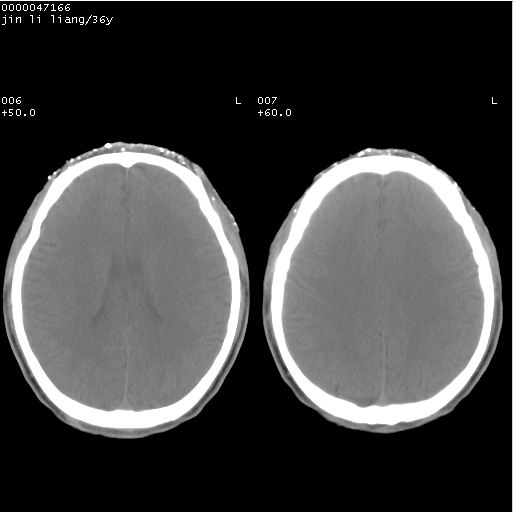

患者 男,36岁。头面部“土炮”炸伤。pe:面目全非,伤口流血不止。

临床诊断:头面部外伤。

颅脑ct轴位平扫(层厚、层距均为10mm),图像如下:

痛心,左眼啊!好在颅内还好。